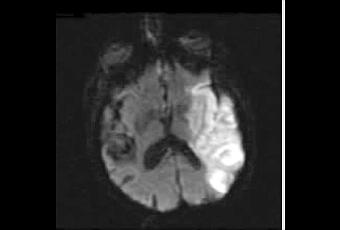

NA-1 appartient à la nouvelle classe des inhibiteurs de PSD95. Lorsque l'apport d'oxygène au cerveau est bloqué, ces inhibiteurs de PSD95 inhibiteurs, tels que NA-1, peuvent perturber la série de réactions biochimiques qui entraîne la mort des cellules du cerveau et contribuer ainsi à préserver le tissu cérébral. Sur les 197 adultes participant à l'essai, alors que les deux tiers des patients ont développé de nouvelles lésions cérébrales après leur chirurgie, les chercheurs constatent que NA-1 a permis de réduire de 41à 47% le nombre et l'ampleur des lésions. Ainsi, les participants ayant reçu NA-1 ont présenté, en moyenne, 3 à 4 nouvelles lésions vs 5 à 7 pour ceux qui n'ont pas reçu NA-1.Aucun événement indésirable grave n'a été identifié comme lié au traitement par NA-1.